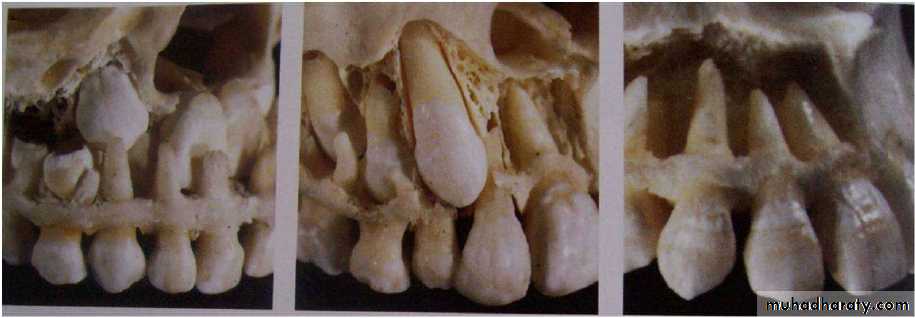

At this stage the permanent

canine is located

immediately above both the

erupting first premolar and

the erupted first deciduous

molar.

As the deciduous teeth

erupts towards the occlusal

plane, the permanent

incisor and canine crypts

migrate forward in the jaws.

The positional changes

between 8 and 10 years ofage need careful

observation for detection of

12

During this stage of development the

canine normally migrates buccally from aposition lingual to the root apex of the

deciduous precursor; however, some

canines do not make the transition from

the palatal to the buccal side of the dental

arch and remain palatally unerupted.